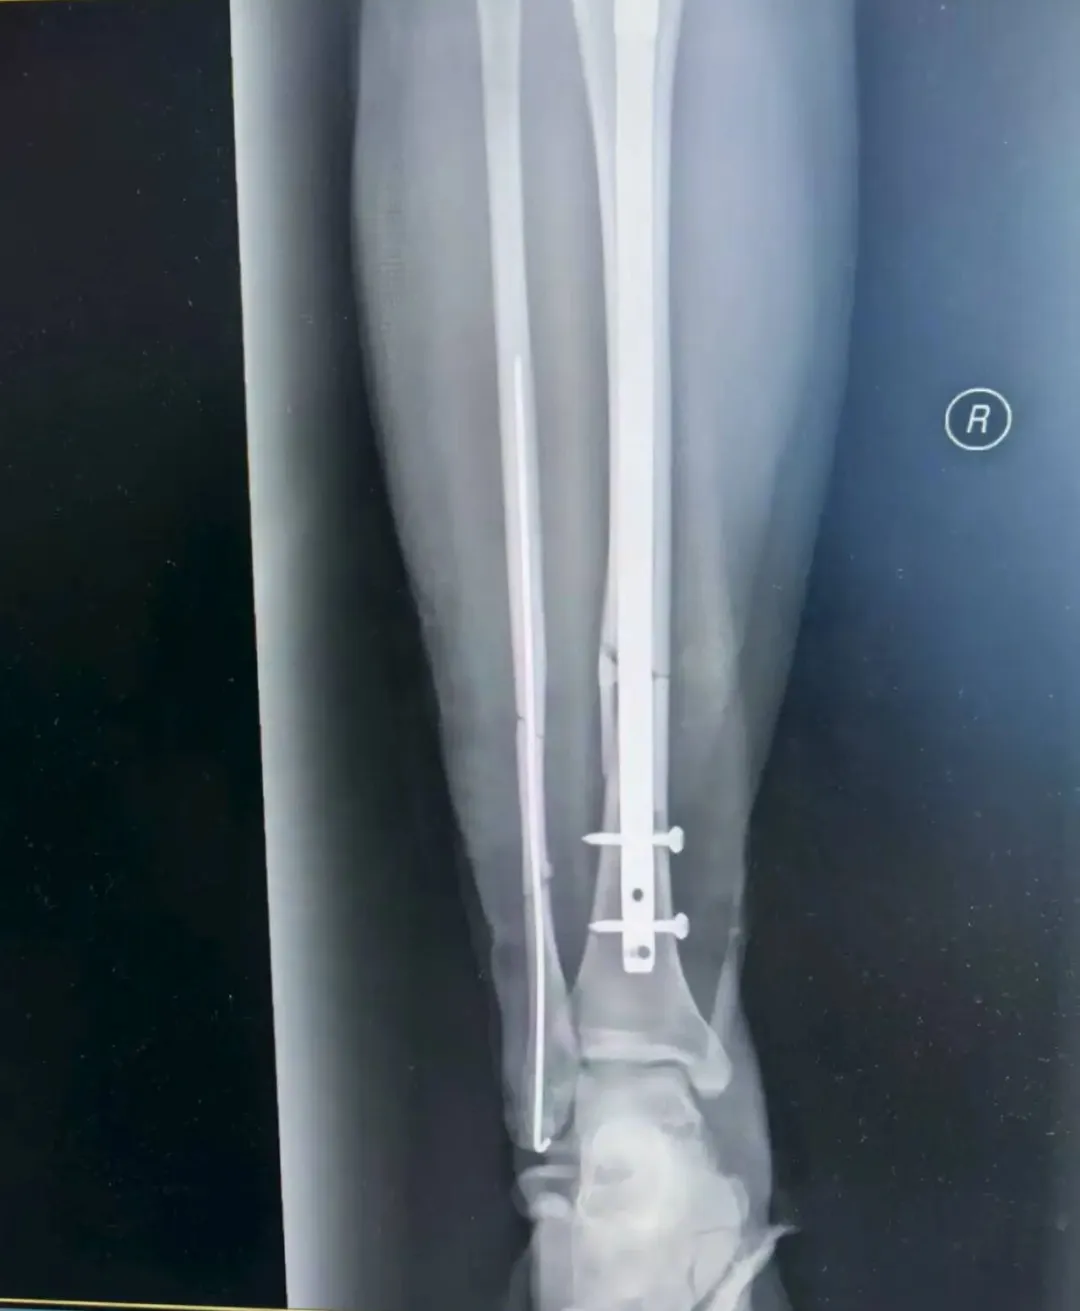

经过诊断,张女士为右侧胫腓骨闭合性骨折,且骨折端移位明显,同时伴有严重软组织肿胀,手足外科孙毅珲主治医师第一时间通过药物与物理治疗控制肿胀、石膏外固定等避免继发性损伤,为后续手术创造安全条件。

考虑到张女士是外地游客,不仅希望骨折能精准复位,还盼着创伤小、恢复快,不耽误后续返程与康复。董伟副主任医师结合影像学资料,综合考虑张女士的身体状况与个人需求,最终确定采用“胫腓骨骨折闭合复位+胫骨髓内钉内固定术+腓骨髓内针内固定术”,全程无需做大切口,通过微创方式实现骨折端精准对位,既能最大程度保护肿胀的软组织,又能显著提升术后恢复速度。

手术由董伟、孙毅珲共同完成,术中借助C臂机实时透视引导,小心翼翼地通过闭合复位技术调整骨折端位置,确保达到解剖复位标准;随后精准植入胫骨髓内钉与腓骨髓内针,完成固定。整个手术过程出血少,术后仅留下几个微小创口,最大程度减少了张女士的痛苦。